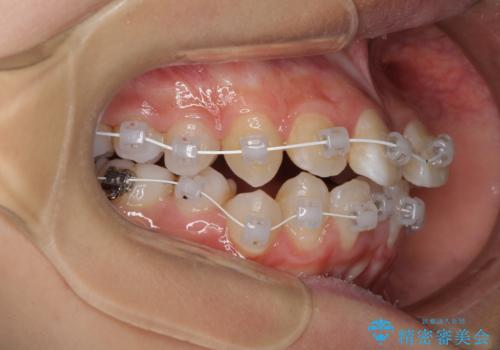

急速拡大装置を用いて上顎骨を側方に拡大し、上顎の叢生を解消するとともに下顎歯列拡大により下顎の叢生も解消することとしました。

急速拡大装置使用直後は著しいスペースが正中に発現するため、ワイヤー矯正を行いますが、今回は治療期間を短くしたいとのことで、上下全体をワイヤー装置にて矯正治療することとしました。

- 審美装置